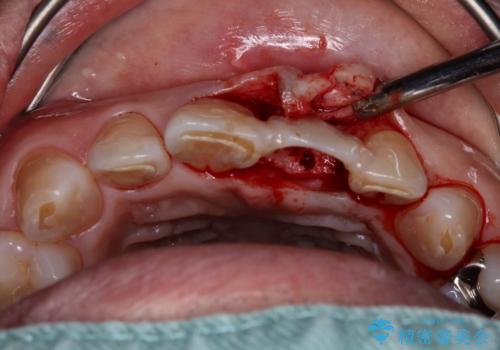

- 歯が朽ちてしまい、歯茎に大きな溝ができていることを気にして来院された患者様です。

インプラント治療を希望されておりましたが、軟組織の欠損が非常に大きいため、骨の回復を待ちながら歯肉の形態を整えていくこととしました。

歯肉形態を概ね回復するタイミングでインプラントを埋入し、補綴治療を行うこととしました。

歯肉移植術による更なる歯肉ラインの改善も検討しましたが、笑ったときに歯肉ラインは唇に隠れてしまうため、現在の位置にて仕上げることとしました。